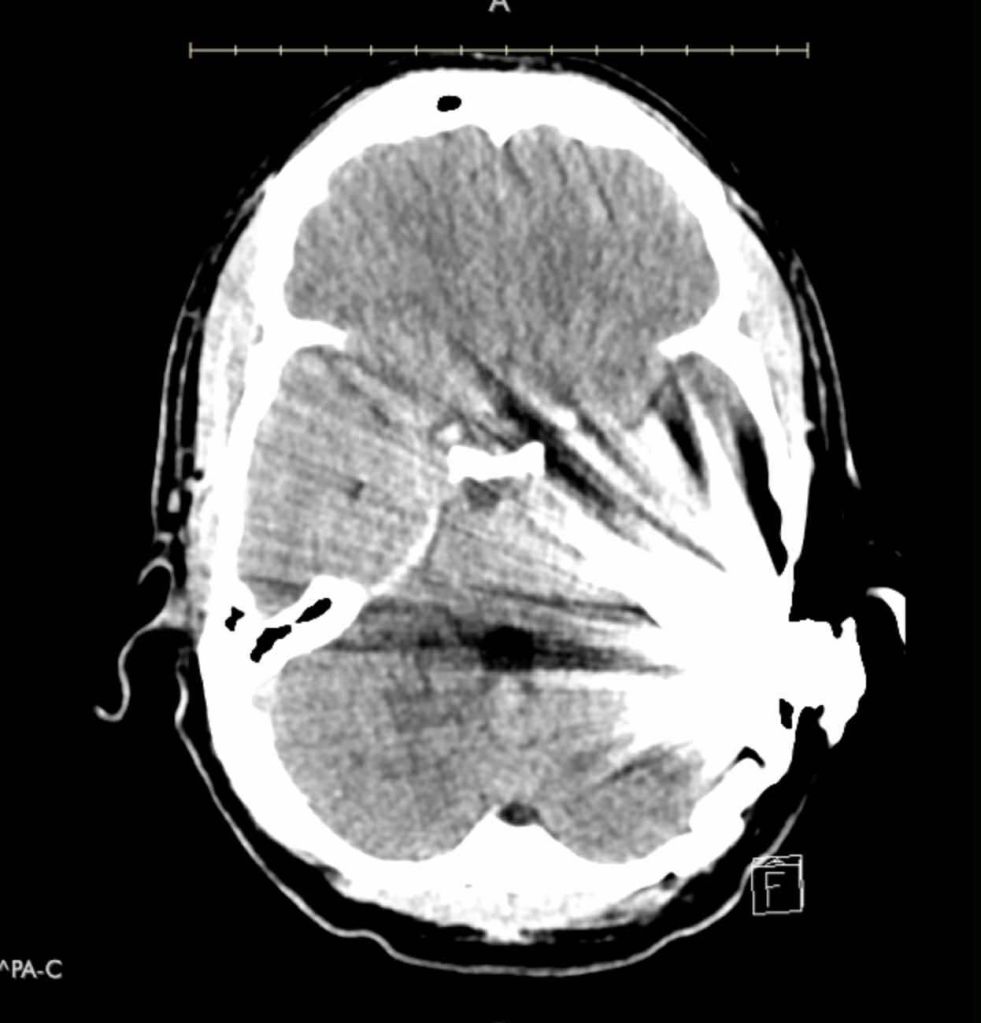

Recently, John reached out to me to share his story. John had lost hearing in one ear from an acoustic neuroma. He had chosen to get a Med-el Bonebridge implant bone anchored hearing device. His ENT doctor had told him it would cast a 17mm shadow for an MRI. However, he had a follow up MRI and it was useless for montioring his tumor. He then learned the literature from Med-el showed the shadow cast from a Bonebridge was 15cm. This is the MRI image he recieved.

He then proceeded to have a CT scan, which was not much better.